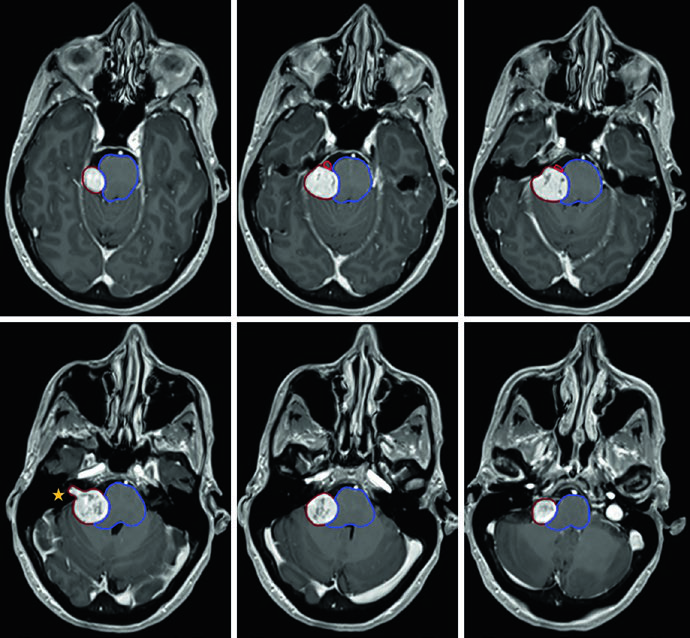

El caso del oligodendroglioma de la Figura 29.5 muestra un paciente tras craneotomía frontotemporal izquierda con resección parcial que involucra la ínsula izquierda, porciones del opérculo y extensión hacia el centrum semiovale izquierdo. El GTV (rojo) abarca la enfermedad residual en FLAIR y la cavidad operatoria. La expansión de 1,0 cm genera el CTV (amarillo), con restricción anatómica fuera de la fosa posterior, cráneo y estructuras de línea media. El PTV (azul) recibe un margen adicional de 0,3 cm.